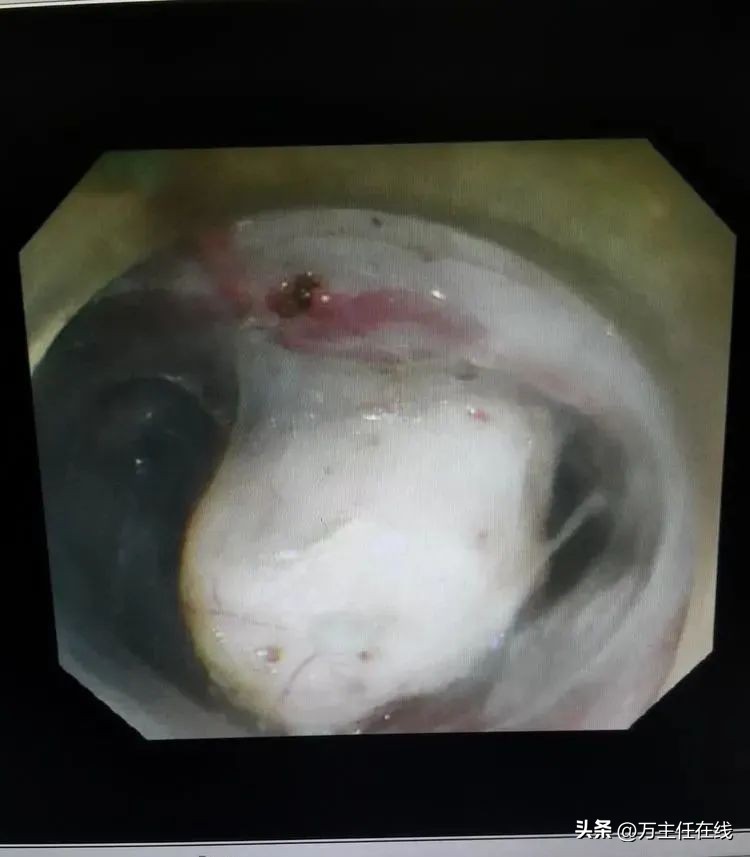

粘膜下隧道游离后,显露部分肿瘤

肿瘤显露近半

游离肿瘤大部

瘤体部分位于纵隔紧贴主动脉弓,即将完整剥除